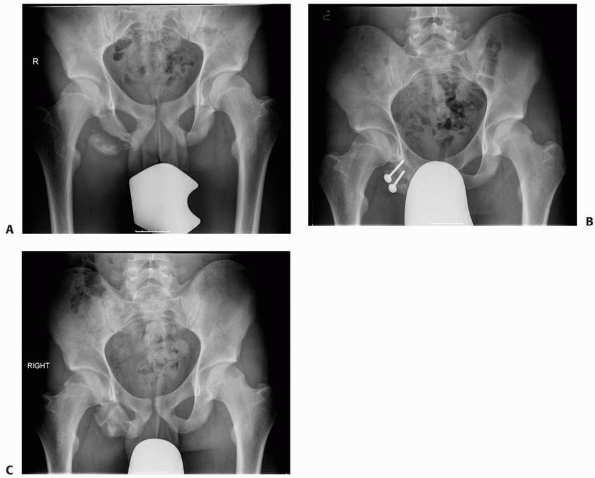

![]() |

FIGURE 20-6 A. A painful ischial apophyseal nonunion in an athlete. B. Fixation of the apophysis. C. Healed apophysis after implant removal. (Courtesy of Dr. David C Scher, Hospital for Special Surgery, NY.)

pelvic avulsion fragments displaced more than 1 to 2 cm (Fig. 20-6).48